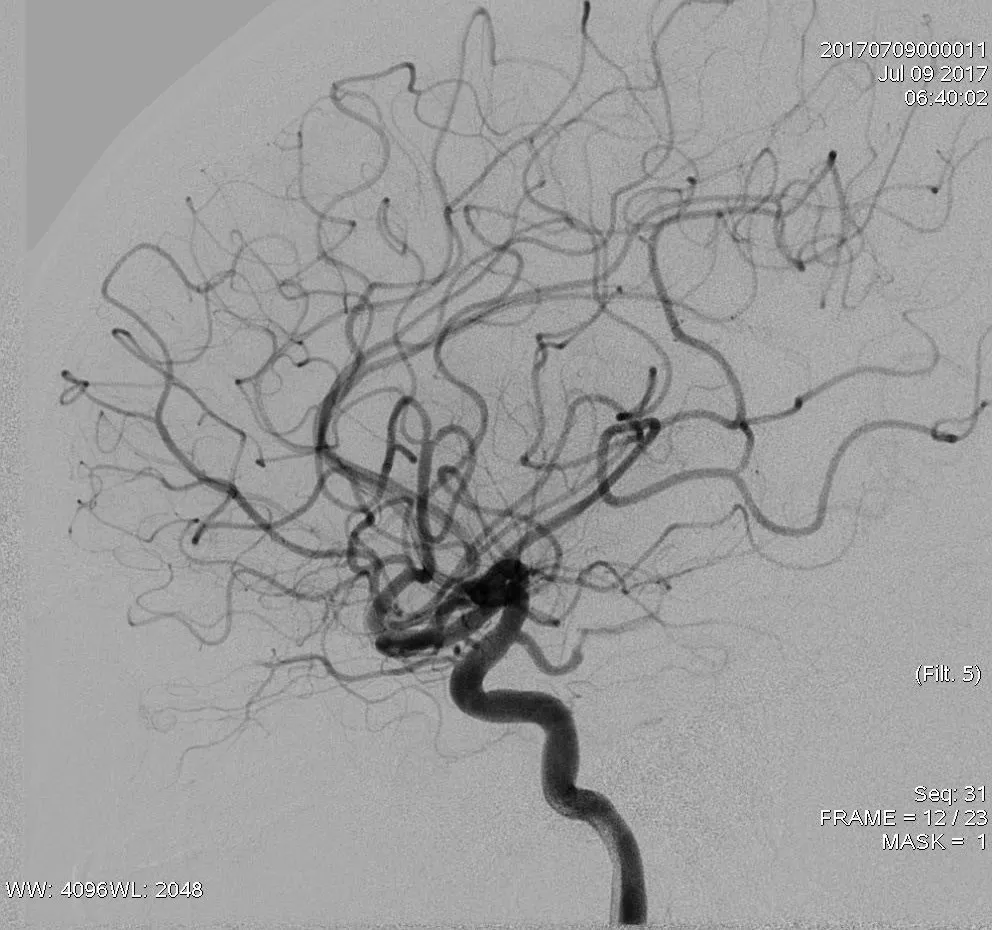

患者发病后1小时40分钟行穿刺。血管造影示,右侧颈总动脉(CCA)中部以远未见显影,术前mTICI分级:0级。

侧支循环评估提示右侧大脑后动脉、大脑前动脉(ACA)皮层支发挥部分代偿作用。

大脑后动脉

大脑前动脉

8F指引导管联合6F Navien中间导管,冒烟证实,右侧CCA中段以远未见显影(A),造影证实,右侧ICA窦部以远未见显影(B)

8F指引导管联合6F Navien中间导管,通过中间导管造影,提示ICA眼动脉段以远未见显影

8F指引导管联合6F Navien中间导管,右侧MCA取栓:微导丝到位;Rebar27导管到位,冒烟证实于血管腔内;6*30mm支架放置MCA-M1段,MCA未见显影,ACA未见显影;表明血栓负荷非常大

双支架放置后造影提示,右侧ACA部分显影,MCA仍血管显影不佳(A),双支架放置4分钟后造影提示,右侧前循环显影更差(B)

最后双支架联合抽吸拉通血栓。造影提示取栓后血管再通,TICI 3级。

取栓后造影:TICI 3级